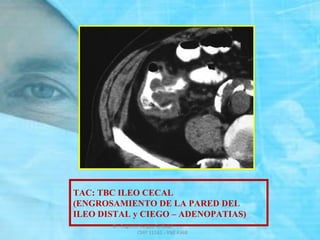

TAC: TBC ILEO CECAL

(ENGROSAMIENTO DE LA PARED DEL

ILEO DISTAL y CIEGO – ADENOPATIAS)